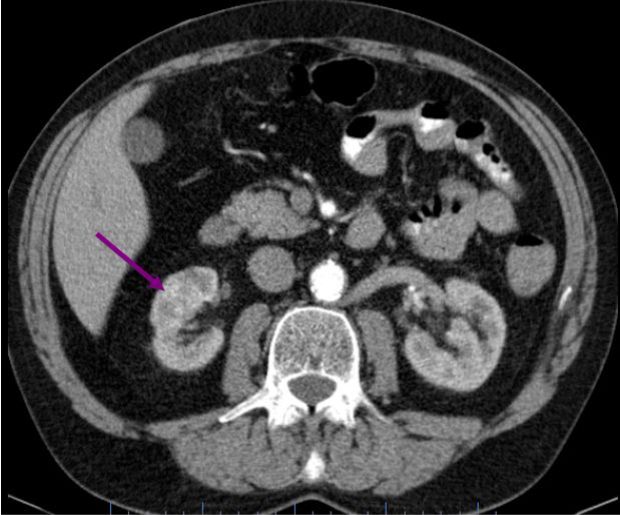

Muž 45 let – potíže s mikcí

Jste lékař urolog a přichází k vám pacient odeslán od praktického lékaře (PL). PL k Vám odesílá muže ve věku 45 let, pro nespecifické mikční potíže, které se objevily po prochlazení. Krev v moči pacient nepozoroval, lékařem to však nebylo došetřeno. Pacient nebyl doposud urologicky sledován, neléčil se.